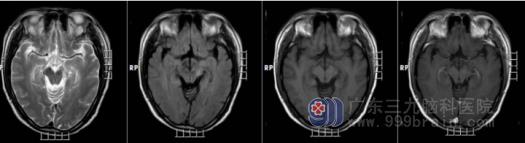

图2 同一名患者,经激素治疗后,病灶明显缩小好转,强化消失。